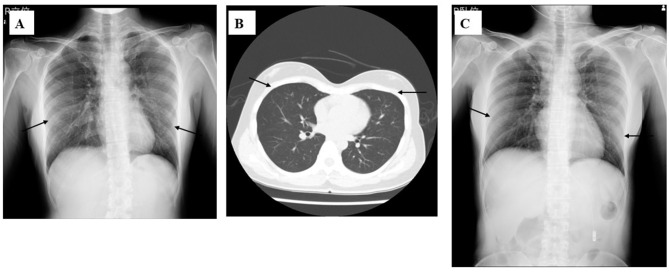

Case series: Four adult cases of M. pneumoniae pneumonia that required admission to the hospital in the 2024-2025 season are presented. Case 1: a 17-year-old male without a specific medical history who was admitted with pneumonia with a severe dry cough. Mycoplasma. pneumoniae genes were detected by multiplex PCR from his sputum. The patient's condition improved with minocycline and corticosteroids for 5 days. Case 2: a 88-year-old man with acute kidney injury who was admitted with severe respiratory failure. Mycoplasma antigen was detected in his pharyngeal swab. He received lascufloxacin drip infusion with corticosteroids for 10 days, and soon improved. Case 3: a 38-year-old woman with maxillary carcinoma and a history of aplastic anemia who was admitted with a severe cough. Mycoplasma antigen was detected in her pharyngeal swab. She received minocycline and corticosteroid drip infusion for 1 week, and finally improved. Case 4: a 74-year-old man with multiple systemic atrophies who was admitted with a severe cough and dyspnea. Mycoplasma antigen was detected from his pharyngeal swab and methicillin-susceptible Staphylococcus aureus (MSSA) was isolated from his sputum. The patient was diagnosed with co-infection with mycoplasma and MSSA. He was treated with sulbactam/ampicillin drip infusion and oral administration of minocycline for 2 weeks, and improved.

Conclusion: All hospitalized adult patients with mycoplasma pneumonia were treated with antibiotics, such as minocycline and fluoroquinolone, along with corticosteroid co-administration, and all of them ultimately improved, although the chest X-ray findings varied. Antibiotics other than macrolides and corticosteroids may be an effective regimen for the treatment of severe mycoplasma pneumonia with potential macrolide resistance.